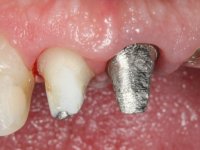

Endodontic treatments were performed and a metalic non screwed intra radicular post was placed on tooth 1.1. An alginate impression was made for laboratory confection of a reinforced acrylic provisional bridge, with teeth 1.1 and 2.2 as abutments and 2.2 as a pontic. After preparation of tooth 1.1 and root preparation of 2.1, the bridge was relined in mouth with self-polymerizable acrylic using a metal post for further retaining the prepared root canal on 2.1. Tooth 2.2 was cut at the gingival level to function as support. In the same session, the impression of the root canal of the 2.1 was made for the laboratory confection of a cast post and core. A double mixture technique with plastic tutor was used after previous canal vaseline with endodontic file and cotton. The provisional bridge was provisionally cemented and the cast post and core was made in the laboratory. Cast post and core cementation was made with resin-reinforced glass ionomer cement and the provisional bridge had to be readjusted to the new situation by removing the post at the site of 2.1. After careful surgical planning, a dental implant was placed, simultaneously with extraction of the root of tooth 2.2. The provisional bridge was placed by resting on the healing screw placed in the implant. The respected osteointegration period was 12 weeks, during which the provisional bridge was relined twice. After complete maturation of hard and soft tissues, definitive impressions were made. The gingival retraction technique was applied with an impregnated retraction cord and impression was performed using double mixture, open tray impression technique. A custom precious metal abutment implant was prepared in the lab, along with 3 metal caps to be used as infrastructures for the metal ceramic crowns. Particular care was taken in the confection of the cervical finishing line of the implant abutment, in order to follow the soft tissues emergence profile. Proof of infrastructures was done in the mouth being evaluated clinically and imagiologically. Collection of color information was done by the ceramist at the office. Ceramic was applied in the laboratory and the finished work was placed in the mouth after approval by the patient. Definitive cementation was made with resin-reinforced glass ionomer cement, and the first crown to be cemented was that of the implant, to facilitate removal of the excess.